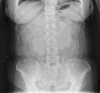

Gallstone ileus (GI) is characterized by occlusion of the intestinal lumen as a result of one or more gallstones. GI is a rare complication of gallstones that occurs in 1%-4% of all cases of bowel obstruction. The mortality associated with GI ranges between 12% and 27%. Classical findings on plain abdominal radiography include: (1) pneumobilia; (2) intestinal obstruction; (3) an aberrantly located gallstone; and (4) change of location of a previously observed stone. The optimal management of acute GI is controversial and can be: (1) enterotomy with stone extraction alone; (2) enterotomy, stone extraction, cholecystectomy and fistula closure; (3) bowel resection alone; and (4) bowel resection with fistula closure. We describe a case to highlight some of the pertinent issues involved in GI management, and propose a scheme to minimize recurrent disease and postoperative complications. We conclude that GI is a rare condition affecting mainly the older population with a female predominance. The advent of computed tomography and magnetic resonance imaging has made it easier to diagnose GI. Enterotomy with stone extraction alone remains the most common surgical method because of its low incidence of complications.